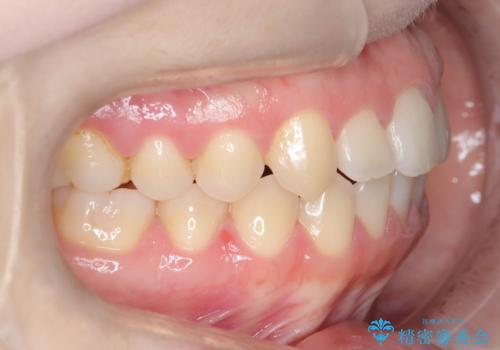

前歯のガタツキ、前歯の噛み合わせ(開咬)をインビザライン治療で治しました

- 前歯のがたつき、噛み合わせが気になるとのことで来院された患者様です。

インビザラインを使用して治療しました。

前歯がしっかり噛んでない状態(開咬)を治すために、前歯にゴムをかける必要があります。ゴムかけは患者様にご協力していただきます。